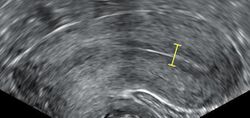

Demonstration of ICSI

The sperm and the egg are incubated together at a ratio of about 75,000:1 in a culture media in order for the actual fertilisation to take place. A review in 2013 came to the result that a duration of this co-incubation of about 1 to 4 hours results in significantly higher pregnancy rates than 16 to 24 hours.[51] In most cases, the egg will be fertilised during co-incubation and will show two pronuclei. In certain situations, such as low sperm count or motility, a single sperm may be injected directly into the egg using intracytoplasmic sperm injection (ICSI). The fertilised egg is passed to a special growth medium and left for about 48 hours until the embryo consists of six to eight cells.